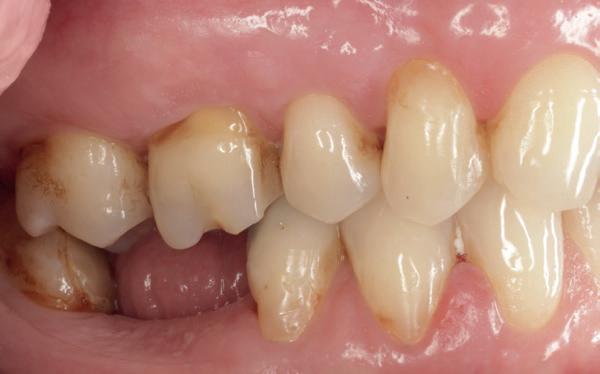

De patiënt werd in de eerste fase gezien door de parodontoloog, implantoloog en restauratief behandelaar. Klinisch werden drie complicerende factoren vastgesteld: inadequate mondhygiëne, een ongunstige occlusale relatie en restauraties met gebrekkige marginale adaptatie met overhang. De patiënt werd opgenomen in het parodontale behandelprotocol.

De diagnose luidde lokaal parodontitis met ernstige furcatie aandoeningen; Stadium IV (vergevorderd); graad C (snel progressief) (afbeelding 7) De elementen die niet te behouden waren, werden geëxtraheerd.

Na afronding van de eerste twee behandelstappen werd parodontale stabiliteit bereikt, zoals waarneembaar op de parodontiumstatus en (röntgen)foto’s (afbeelding 6, 8). De patiënt toonde aantoonbare verbetering in mondhygiëne (afbeelding 4) en bleef gemotiveerd om de behandeling voort te zetten.

Restauratieve fase

Planning en voorbereiding